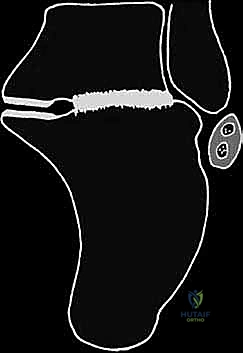

- دمج المفصل تحت الكاحل (Subtalar Arthrodesis):

في الغالبية العظمى من حالات سوء الالتئام، يكون المفصل تحت الكاحل قد تدمر تماماً بسبب الخشونة والاحتكاك. الحل الجذري والنهائي للألم هنا هو "دمج" أو "تثبيت" هذا المفصل. يقوم الدكتور هطيف بتنظيف الغضاريف التالفة بالكامل، ووضع العظام في وضعها التشريحي الصحيح، ثم تثبيتها باستخدام براغي معدنية قوية جداً (Screws) لتلتحم وتصبح عظمة واحدة صلبة خالية من الألم.